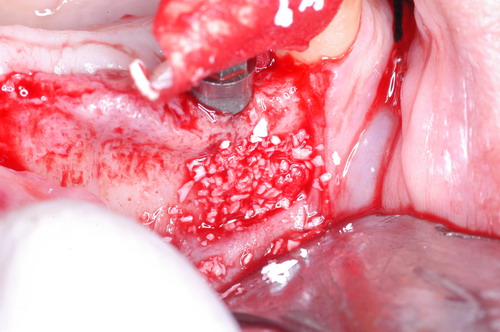

EL USO DEL ARCO GÓTICO DE GYSI , MEDIANTE UNA BÓVEDA PALATINA Y UN APOYO CENTRAL ÚNICO (BO PA YA CU) , EN LA UBICACIÓN DE LA RELACIÓN CÉNTRICA EN UN CASO DE GRAN LAXITUD TENDINOSA CAPSULAR. EL PACIENTE SE PRESENTA A CONSULTA CON UNA EDENTACIÓN PARCIAL, Y GRADO DE MOVILIDAD EXTREMO EN TODAS SUS PIEZAS REMANENTES. SE ESTUDIA EL CASO RADIOGRÁFICA Y CLÍNICAMENTE , Y EL PACIENTE RELATA ESTAR EN ESE ESTADO DESDE HACE MUCHO AÑOS. AL MANIPULAR LA MANDÍBULA EN UN INTENTO DE CONOCER EL ESTADO MUSCULAR DEL SISTEMA, SE OBSERVA UNA GRAN LABILIDAD TENDINOSA CAPSULAR QUE SE MANIFIESTA EN UNA HIPER LAXITUD EN LOS MOVIMIENTOS MANUALMENTE INDUCIDOS DE AMBOS CÓNDILOS DENTRO DE LA CAVIDAD. SE TOMAN IMPRESIONES Y SE MONTA EN UN ARTICULADOR SEMI AJUSTABLE , CORTANDO EN EL YESO LAS PIEZAS QUE SERÁN EXTIRPADAS , CONSERVANDO UNICAMENTE , AMBOS PRIMEROS PREMOLARES INFERIORES , QUE SERÁN UTILIZADOS PARA RETENER MEDIANTE RETENEDORES ELÁSTICOS LA PRÓTESIS INFERIOR , EN LA PRESUNCIÓN DE LA HIPERMOVILIDAD A QUE SERÁ SOMETIDA DADO QUE EN LA GRAN REABSORCIÓN ÓSEA , ES FRECUENTE EL ACERCAMIENTO DE TODAS LAS INSERCIONES MUSCULARES A LA PORCIÓN SUPERIOR DEL REBORDE ÓSEO , LO QUE ATENTARÁ CONTRA LA ESTABILIDAD DE DICHA PRÓTESIS PROVISIONAL. EN UNA PRIMERA SESIÓN CLÍNICO QUIRÚRGICA , SE EXODONCIA TODO EL SECTOR INCISIVO Y CANINO INFERIOR , Y AL OBSERVAR EL REMANENTE ÓSEO CANINO DE AMBOS LADOS , SE IMPLANTA EN FORMA INMEDIATA . TANSCURRIDOS DOS MESES , DONDE LA CICATRIZACIÓN ES ADECUADA , Y LA DINÁMICA MANDIBULAR ACEPTABLE , SE PROCEDE A LA ETAPA QUIRÚRGICA IMPLANTARIA MEDIANTE IMPLANTES SEMI SUMERGIDOS, CON ALGUNAS ZONAS DE REGENERCIÓN ÓSEA GUIADA FIG17 FIG18 FIG19 FIG26 DURANTE LA ETAPA DE CICATRIZACIÓN DE ESTE NUEVO ABORDAJE QUIRÚRGICO , SE ENDODONCIAN AMBOS PREMOLARES INFERIORES CONSERVADOS , LOS QUE EN UN FUTURO , CUANDO YA NO SIRVAN PARA RETENER LA PRÓTESIS REMOVIBLE PROVISORIA INFERIOR , SERÁN CORTADOS COMO RESERVA DE CAPITAL ÓSEO O BIEN COMO ELEMENTO RETENEDOR ANTE CUALQUIER TIPO DE INCIDENCIA IMPLANTARIA. ABORDAMOS LA ETAPA PRIMARIA PROTÉTICA , UNA VEZ TRANSCURRIDOS TRES MESES, MEDIANTE LA UTILIZACIÓN DE CUBETAS INDIVIDUALES , A LAS QUE REALIZAMOS UN RECORTE MUSCULAR EN BASE A STENS VERDE , COMO SI DE UNA PRÓTESIS COMPLETA SE TRATARA. DE ESE MONTAJE OBTENEMOS DOS RODETES DE METACRILATO , PERFECTAMENTE ADAPTADOS A LOS MODELOS FUNCIONALES , A LOS QUE LES OTORGAMOS LA PLANIMETRÍA DERIVADA DEL PARALELISMO CON EL PLANO DE FRANKFURT , Y UNA ALTURA (DV) QUE RESULTA DE LOS MÉTODOS MÉTRICOS DE DIMENSIÓN VERTICAL… Y QUE NOS SERVIRAN ADEMÁS DE TOMAR UNA NUEVA IMPRESIÓN FUNCIONAL MEDIANTE RECORTE MUSCULAR , PARA ADAPTAR UN DISPOSITIVO CONSISENTE EN UNA BÓVEDA PALATINA SUPERIOR , Y UN TORNILLO CENTRAL INFERIOR , LOS QUE DESPUÉS DE UN ENTRENAMIENTO ADECUADO DEL ENFERMO , NOS PERMITIRÁ REPRODUCIR EN EL BÓVEDA , EL ARCO GÓTICO DE GYSI , ENCONTRANDO DE ESTA MANERA LA OCLUSIÓN EN RELACIÓN CÉNTRICA. ACTUALMENTE ESTE MÉTODO HA SIDO RECREADO MEDIANTE LA DENOMINACIÓN DE: FIG50 FIG51 FIG52 OBTENIDO EL DIBUJO DEL ARCO GÓTICO , INSINUAMOS EN EL VÉRTICE DEL MISMO UNA PERFORACIÓN QUE FIJARÁ LA PUNTA DEL TORNILLO EN ESA POSICIÓN: RELACIÓN CÉNTICA FIG55 FIG56 FIG57 CON ESTOS PARÁMETROS SE CONSTRUYEN DOS SOBREDENTADURAS ABROCHADAS EN RÓTULAS SUPRA IMPLANTES , QUE LE OTORGAN FIJACIÓN SUFICIENTE , DANDO A LA OCLUSIÓN TODOS LOS ELEMENTOS DE UNA: OCLUSIÓN MUTUAMENTE COMPARTIDA, REFERENCIA II CON UN ESQUEMA OCLUSAL DE : FUNCIÓN DE GRUPO BILATERAL POSTERIOR DE ACCIÓN CANINA DESPUÉS DE LAS REVISIONES PERTINENTES A LA SEMANA , EL MES Y LOS SEIS MESES DE TERMINADA LA REHABILITACIÓN , SE CITA AL ENFERMO PARA UN NUEVO CONTROL AL AÑO Y MEDIO Y SE OBSERVA UNA PERFECTA SITUACIÓN TISULAR , CLINICA Y RADIOGRAFICAMENTE CONTROLADA , Y ADEMÁS LA PERMANENCIA DEL MISMO ESQUEMA OCLUSAL OTORGADO DESDE EL PRINCIPIO. SE CONTROLA RADIOGRAFICAMENTE Y SE DA EL ALTA DEFINITIVA RECOMENDANDO EL CONTROL DOS VECES AL AÑO. REFERENCIAS: I : II. : III: